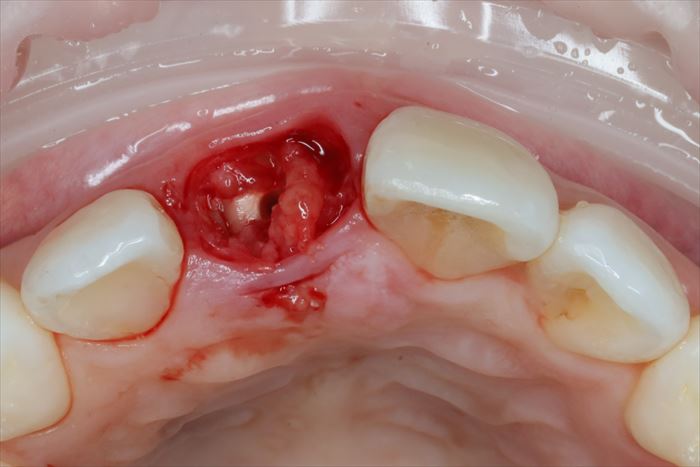

残っていた歯根を抜歯し、顕微鏡下で抜歯窩内部の掻爬を終えました。

心配していた唇側の骨は無事に保存できました。

ここからはドリリングを行い、インプラントを植えるためのインプラント床(しょう)を形成します。